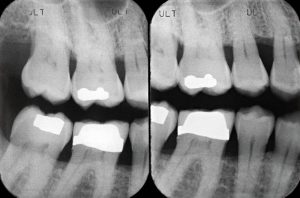

Radiografía Bitewing (aletas de mordida)

Capturan los dientes superiores e inferiores en una sola imagen. Muestra la unión entre los dientes y las encías, identificando caries entre ellos y permite monitorear la pérdida ósea causada por enfermedades periodontales.